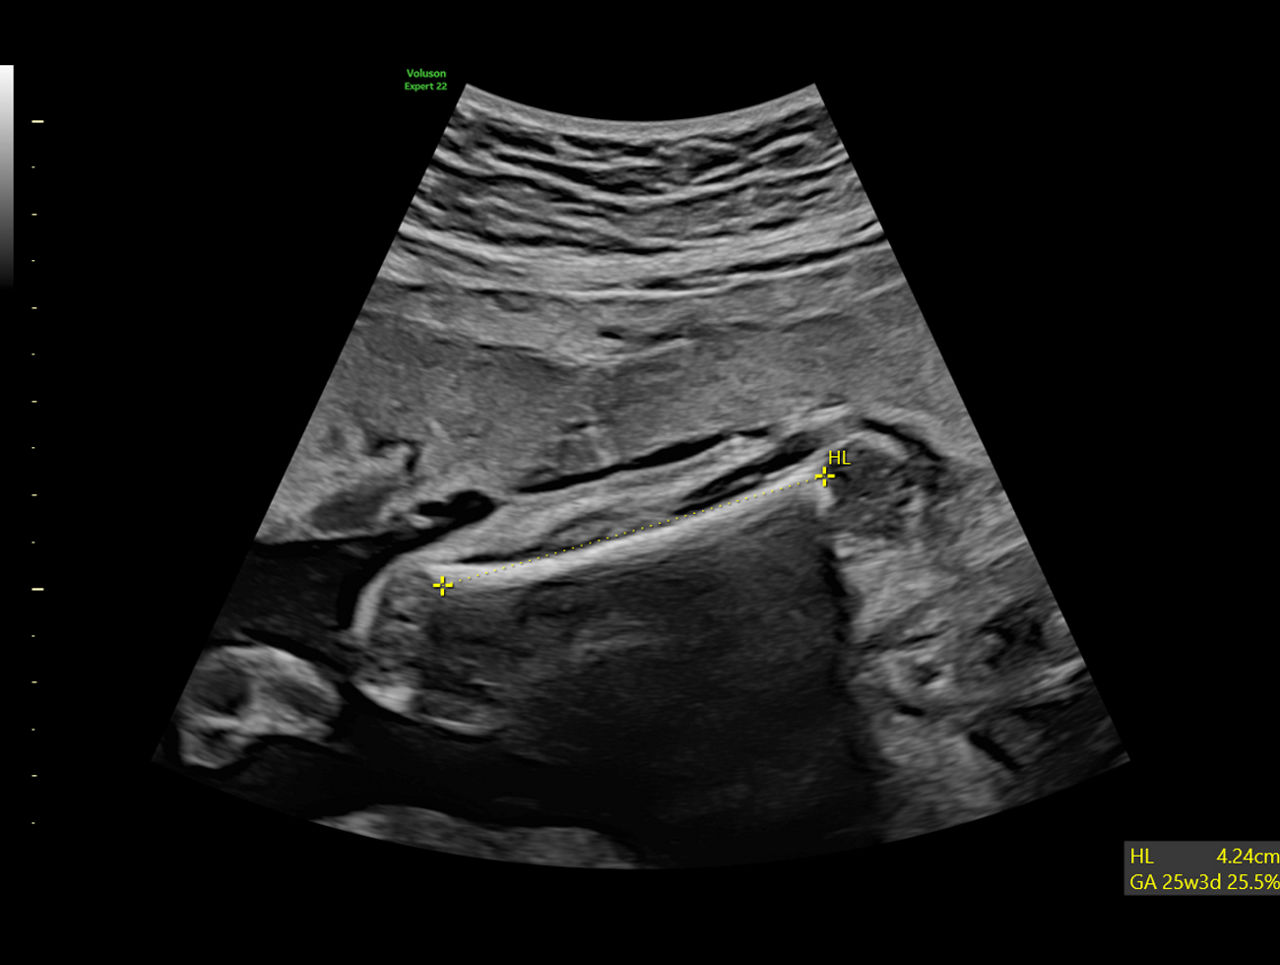

Repetitive tasks are a daily challenge especially in fetal development assessment. SonoBiometry helps reduce keystrokes and improves exam time by automatic caliper placement and fetal measurements of bi-parietal diameter (BPD), head circumference (HC), abdominal circumference (AC), femur length (FL), humerus length (HL), lateral ventricle, cerebellum, and cisterna magna.

Clinical-Image-of-SonoBiometery